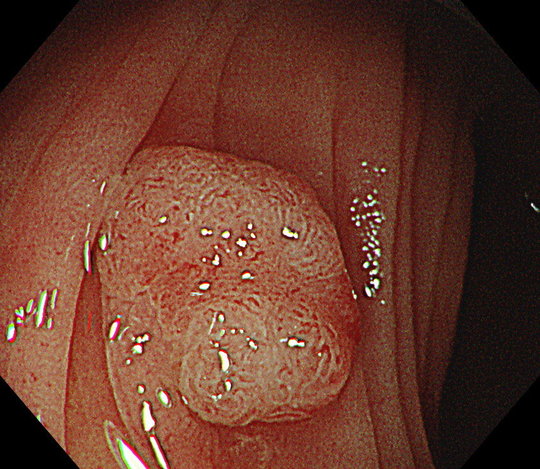

腸を伸ばさずに検査を行うことは、ポリープを見つける観察と切除治療の時にも、大きな効果があります。大腸内視鏡で一番大切なことは、ポリープがないか見落としがないようにしっかり観察すること、そして見つかったポリープを切除するべき病変かどうか正確に診断し、切除が必要な病変であれば、安全かつ確実に病変を切除することです。

最高画質下で観察することで、病変が腫瘍であるのか、悪性のがんであるのかどうか、手術が必要か、それとも内視鏡で切除できるのか、適切な判断をする上で非常に有用です。最新機器による最高画質に加え、腸を伸ばさない優しい内視鏡は、余分な力が腸にかからないため、観察も極めてスムーズに行うことができます。ポリープ切除の時にも確実に病変を治療することができ、内視鏡治療の精度が格段に上がります。

大腸内視鏡検査では、ポリープや大腸がんを見落としなく観察し、確実に発見することがまず重要です。

さらに桐山クリニックでは、病変発見時に、約80倍まで拡大観察することが可能な拡大内視鏡を標準使用しています。この内視鏡を使用することで、病変が腫瘍であるかどうか、切除が必要かどうか、何度も検査をすることなく、ボタン1つで評価することができます。